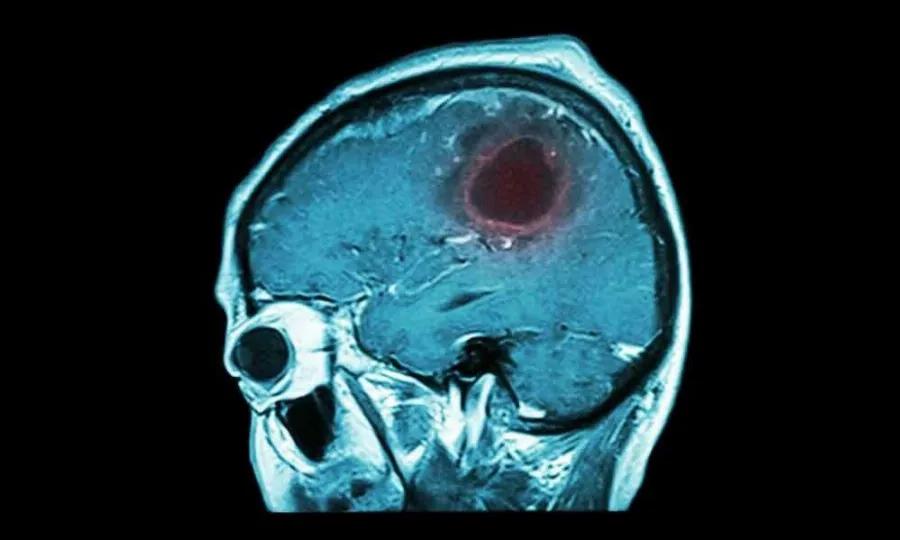

Όγκοι εγκεφάλου: Συμπτώματα και σύγχρονη αντιμετώπιση

Οι όγκοι εγκεφάλου αποτελούν ένα από τα πιο συνήθη προβλήματα της νευροχειρουργικής. Μια πολύ απλή και ταυτόχρονα βασική διάκρισή τους είναι σε πρωτοπαθείς, που προέρχονται από τον ίδιο τον εγκέφαλο και τα περιβλήματά του, και σε δευτεροπαθείς, αυτούς που ουσιαστικά προέρχονται από όγκους που βρίσκονται σε άλλο σημείο του σώματος. Εξίσου σημαντική είναι η διάκρισή των πρωτοπαθών όγκων σε καλοήθεις και κακοήθεις, ενώ οι δευτεροπαθείς είναι εξ ορισμού κακοήθεις.

Όγκοι εγκεφάλου: Πώς καταλαβαίνω ότι υπάρχει περίπτωση να έχω;

Το συχνότερο σύμπτωμα των όγκων εγκεφάλου είναι ένα σταδιακά επιδεινούμενο νευρολογικό έλλειμμα, όπως αδυναμία ενός άκρου, πρόβλημα στη κατανόηση ή εκφορά λόγου (δυσφασία), αλλά και ο επιδεινούμενος πονοκέφαλος, μειωμένο επίπεδο συνείδησης, επιληπτικές κρίσεις κα. Ειδικά οι όγκοι υπόφυσης μπορούν να εκδηλωθούν με ενδοκρινολογικές διαταραχές. Πολλές φορές, οι όγκοι εγκεφάλου είναι τυχαία ευρήματα σε απεικόνιση για άλλο λόγο.

Όγκοι εγκεφάλου: Ποιες εξετάσεις χρειάζεται να γίνουν;

Συνήθως η αρχική διάγνωση γίνεται με αξονική τομογραφία, αλλά τις περισσότερες φορές για τον πλήρη χαρακτηρισμό μια βλάβης απαιτείται μαγνητική τομογραφία με ενδοφλέβιο σκιαγραφικό και ίσως ειδικές ακολουθίες. Κάποιες φορές (όπως σε όγκους υπόφυσης) αιματολογικές εξετάσεις είναι απαραίτητες. Τέλος, σε ορισμένες περιπτώσεις απαιτείται ακόμα και βιοψία της βλάβης, με την τελική διάγνωση να δίνεται από τον παθολογοανατόμο.